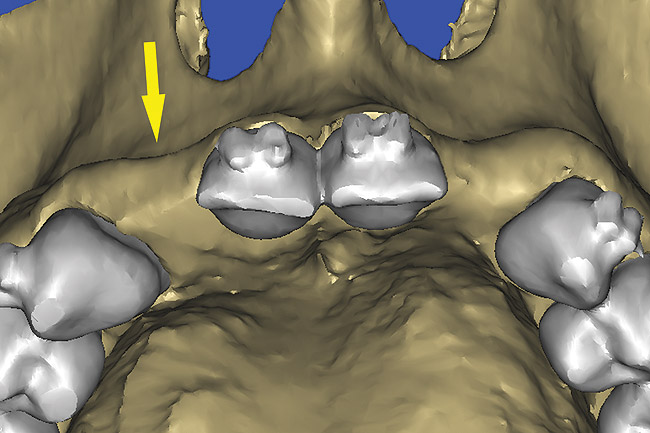

Confirmation with Interactive 3D Imaging

After the basic plan had been established, it was re-evaluated using interactive 3D images. The reconstructed 3D view of the maxilla clearly illustrated the extent of the bilateral facial concavities, and the root eminences of the adjacent and posterior teeth (Figure 12). The placement of the virtual implants then was evaluated to ensure that the facial cortical plate was not perforated (Figure 13). The implants were labeled individually as “7” and “10,” with the simulated yellow abutment projection indicating the facial-lingual inclination through the bone to the level above the incisal edge of adjacent teeth. The ability to gain a better understanding of these individual root forms cannot be underestimated. The dental literature has suggested certain parameters for placing implants near teeth and implants next to other implants. However, there is little scientific 3D documentation to support these suggested rules.5-10 The use of an interactive treatment-planning software application permits closer scrutiny of previously difficult-to-visualize areas, and can now be used to redefine perceptions of spatial positioning of implants, especially when in close proximity to natural tooth roots, vital anatomy, and adjacent implants.27-29

Using different masking (segmentation) and threshold Hounsfield unit values, several new 3D bone volumes can be created which offer invaluable information. To help determine the final position of each implant a new bone model was created with a Hounsfield unit value of 1480, which eliminated all but the densest objects included in the scan data. (Results may vary depending on the CBCT machine used.) The inner and outer layers of bone were removed, leaving the underlying enamel and root structure of the teeth (Figure 14). After the bone had been stripped away, the root inclinations were examined closely. The most striking findings confirmed the rotated position of the right central, while revealing the slight mesial dilaceration of the root apex, which converged on the space needed for the path of the potential implant (Figure 15). The schematic shapes of the proposed implants were visualized for the right and left lateral spaces in different rotations of the 3D maxillary arch. It was at this point that a determination was made as to the appropriate implant shape and type that would fit the available space while avoiding encroachment on adjacent tooth roots. A tapered design implant (Tapered Screw-Vent®, Zimmer Dental, www.zimmerdental.com) was chosen from the large virtual library. With the SIMPlant software, the virtual library contains data from dozens of implant manufacturers and realistic computer-aided design representations as seen in Figure 16 through the translucent bone. The position of the left implant can be visualized with adequate mesial-distal distance between adjacent tooth roots (Figure 17) and a more delicate placement (Figure 18).

By using interactive treatment-planning software, the author was able to assess implant-to-tooth distances based on actual undistorted measurement of distances at both the crest (Figure 22) and the apex (Figure 23) of the implant. Additionally, the ability to section the 3D model allowed extremely accurate virtual implant placement, ensuring 2 mm of facial and palatal bone surrounding the implant (Figure 24). Using advanced masking tools, further manipulation of the 3D maxilla provided an unparalleled appreciation not only of the potential implant receptor sites, but also of the alveolar complex of each existing tooth and root morphology (Figure 25).

Figure 29  VIRTUAL PLANNING AND SURGERY The information gained from the 3D model was confirmed when the flaps were elevated.

Figure 29